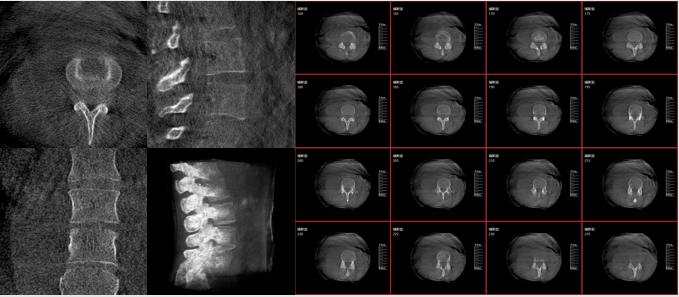

從下圖中可以看到二維影像能夠提供目標區域在某一個平面的重疊影像,雖然因為人體不同組織的密度差異,使得圖像具有較為豐富的信息量,但組織間的相互重疊還是會出現,諸如空間位置等眾多信息在影像中遺失或不可辨認的情況,影響了醫生對信息的收集與應用。

術中二維影像

而三維影像的MPR圖像組可以通過不同平面的切分,使成像區內更豐富的信息得以呈現。尤其是二維影像無法涉及的橫斷面,提供了另一個空間維度的信息量。

術中三維C臂的優勢:三維影像功能

術中三維C臂影像